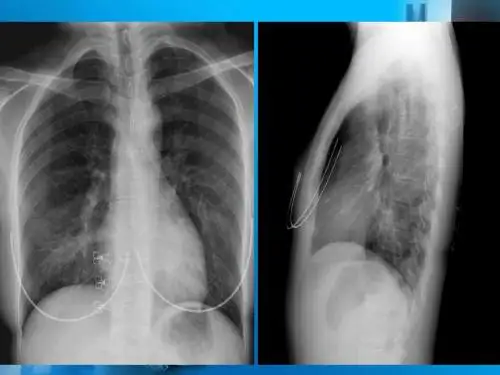

方法:报告经手术与病理证实肺隔离症18例,其中X线胸片18例,支气管碘油造影5例,CT 13例,MRI 4例。

结果:X线表现为肺内肿块7例,大片状影11例,其中病灶内有透光区9例; CT表现为肺内片影及团块影,其内具有含气囊腔或液气平面囊肿,共发现异常动脉供血5例。

MRI可见到病灶内含气液改变及异常血管影。

结论:对肺隔离症的诊断, CT与MRI结合可取代普通X线、断层摄影、支气管造影及主动脉造影。

2 结果2.1 X线表现本组18例,发生在右下肺4例,左下肺14例,病变均偏后,其主要部分位于两肺下叶后基底段区域。

11例为大片状高密度阴影,境界比较模糊,其中4例密度均匀,9例密度不均,病灶内可见到一个或多个大小不等的透光区,较大者尚可见到液气平面;X线表现为团块状阴影7例,境界清楚,密度均匀。

2.3 CT检查所见18例X线表现为片状阴影者,13例行CT扫描,其中4例密度比较均匀,另9例密度不均,可见到含气囊腔,囊腔内有液气平面1例;7例X线表现团块影者4例做CT检查,亦表现为实质性肿块,3例病灶内有密度低区,2例病灶周围有肺气肿改变。